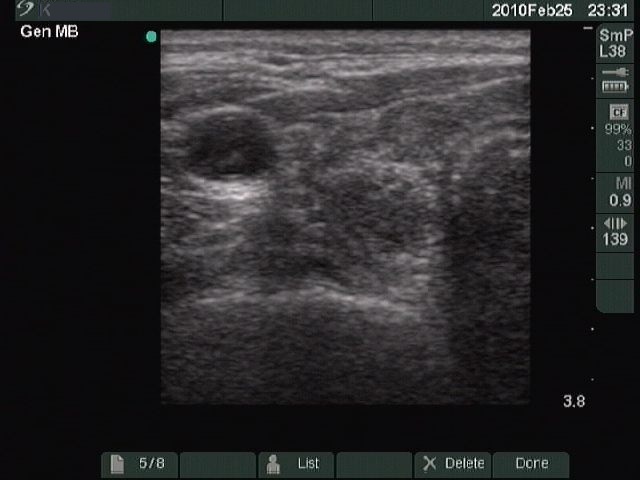

Chronic lymphocytic thyroiditis - Case 49. |

Clinical presentation: a 49-year-old woman with a newly discovered hypothyroidism (TSH 31.7 mIU/L) and a thyroid nodule in a previous sonographic report.

Ultrasonography: typical picture of Hashimoto's thyroiditis without any nodules.

Cytological report: benign Hashimoto's thyroiditis.